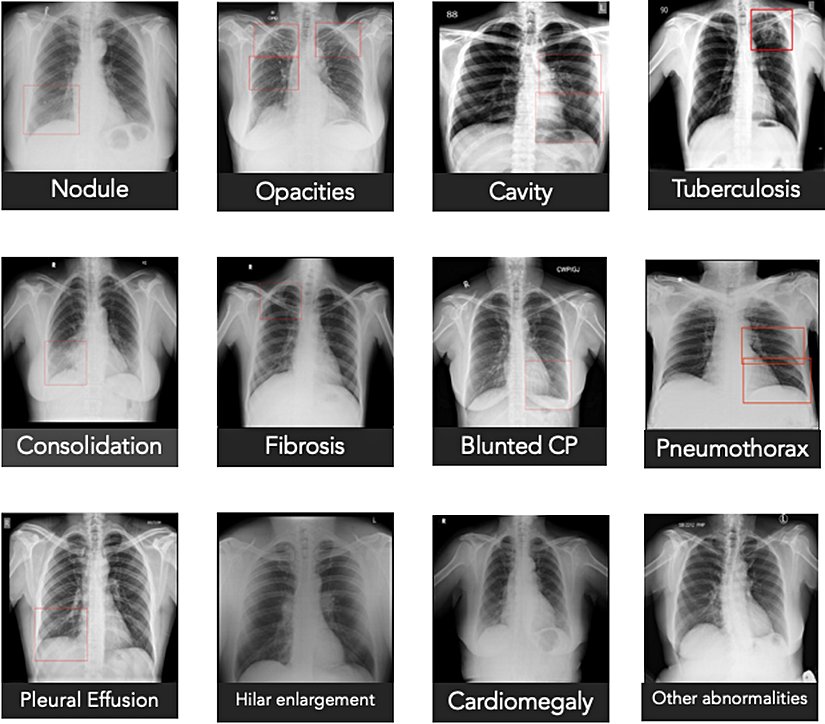

Qure.ai qXR sistemi sık görülen akciğer anomalilerini tespit etmek için derin öğrenme modelleri kullanmaktadır. COVID-19’a uyarlarken uzmanlara danışarak ve literatüre başvurarak COVID-19 pnömonisine ilişkin tipik özellikler değerlendirmeye alınmıştır. Bu bilgiler qXR’ye kodlanmış ve böylece bu enstrüman bu tarz bir görüntüyü taradığında covid-19 enfeksiyonu riskine ilişkin hesaplamalar yapacak duruma getirilmiştir. On bir görüntüyü kapsayan bir ön geçerlik çalışması COVID-19 hastalarının %95 hassasiyetle tespit edilebildiğini göstermiştir.